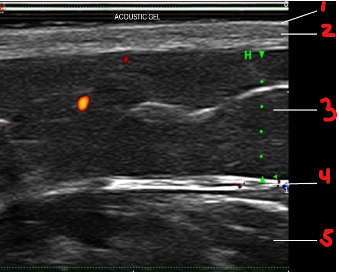

Identify this image.

Layers of skin

Epidermis

Dermis

Hypodermis or subcutaneous adipose tissue

Fascia

Muscle